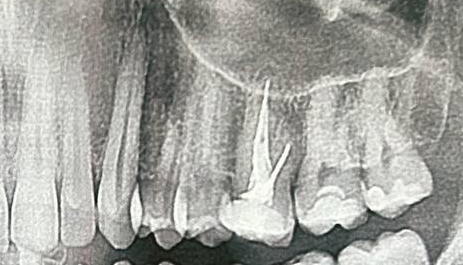

Ещё первый сказал, что у меня только 26 и 27 с кариозной полостью. А второй сказал, что только 16 и 17.

Оба ебланы?